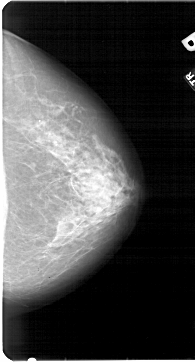

A_1954_1.RIGHT_MLO

RIGHT_CC LINES 5416 PIXELS_PER_LINE 2911 BITS_PER_PIXEL 12 RESOLUTION 43.5 NON_OVERLAY